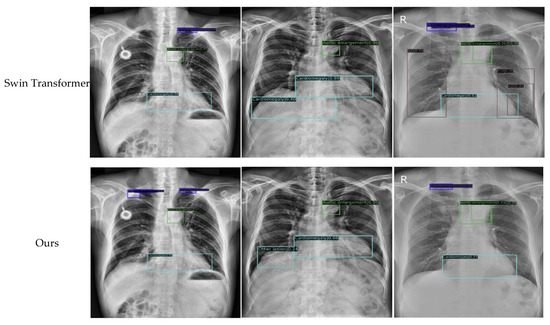

Figure 8.

Detection examples of the compared methods.

First, the proposed method achieved the highest mAP of 0.362, which was 3.2% higher than that of cascade R-CNN (baseline) and 4.8%, 5.6%, 11.3%, and 2.6% higher than that of TridentNet, Libra R-CNN, Sparse R-CNN, and Swin Transformer, respectively. Second, different models were suitable for different types of chest anomaly detection, but our model achieved the highest AP in most categories; that is, we achieved the best performance in five out of the fourteen categories. For example, Libra R-CNN achieved a superior detection precision in pleural effusion, whereas Sparse R-CNN was suitable for detecting large-scale chest abnormalities such as aortic enlargement. Another recently published method that has to be mentioned is Swin Transformer, which showed good potential in the anomaly detection of chest X-rays and achieved the highest AP in three categories, i.e., calcification, pneumo-thorax, and pulmonary fibrosis. However, the proposed method achieved the best results in most categories, including large-scale and small-scale abnormalities, such as infiltration, atelectasis, pleural thickening, consolidation, and cardiomegaly.

Second, by observing the anomaly detection examples shown in Figure 8, visual comparisons also proved that the proposed method generally achieved more accurate detection results, and that our approach could effectively identify the specific locations of various types of chest anomalies. Even for small targets, our method exhibited a high degree of coincidence with the ground truth. This was mainly due to the fact that we improved the backbone networks with embedded local features and context information. Moreover, with the optimized feature fusion process, information from different scales was rationally used to obtain a more accurate prediction region.